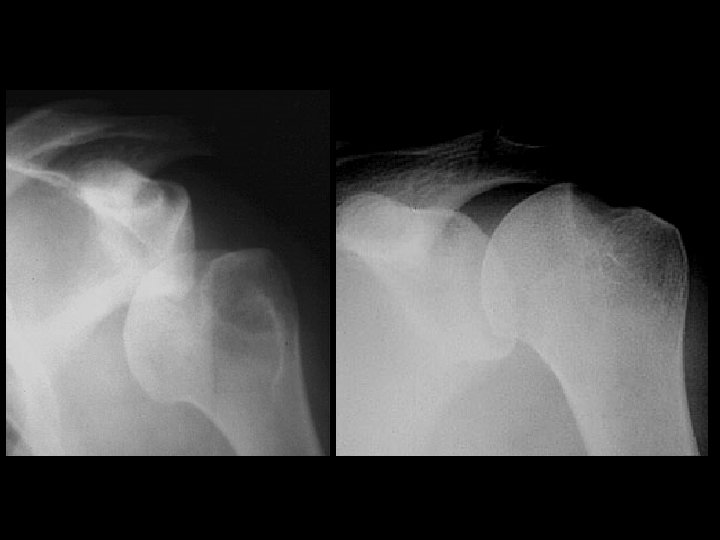

Hill-Sachs Deformity and Osseous Bankart Lesion • • • Findings: – Impaction fracture of the posterolateral humeral margin (Hill -Sachs) – Fracture of the osseous glenoid rim (Bankart) – secondary osteoarthritis Related to repeated anterior dislocations (shoulder instability) Bankart lesion is typically only of the cartilaginous labrum, best seen on MRI